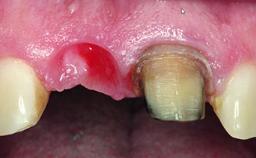

A 49-year-old female patient was referred for implant therapy to replace the upper right central incisor (tooth 11). The tooth had been assessed by an endodontist who diagnosed a vertical fracture of the root. The tooth had a hopeless prognosis and needed to be extracted. The patient was healthy and was not taking any medications. She was allergic to penicillin. The patient had high esthetic demands but her expectations were realistic. The extraoral examination revealed no facial asymmetries. The right temporomandibular joint demonstrated an opening click but was otherwise asymptomatic. The lip line was high with a significant gingival display.

Soft Tissue Anatomy Intact Defective

Soft Tissue Contour and Volume Ideal